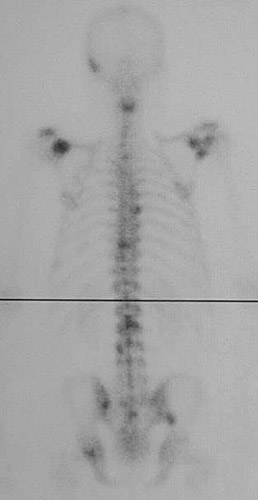

This nuclear medicine bone scan reveals multiple areas of increased uptake, which are the darker foci, such as in the vertebral column representing metastases.